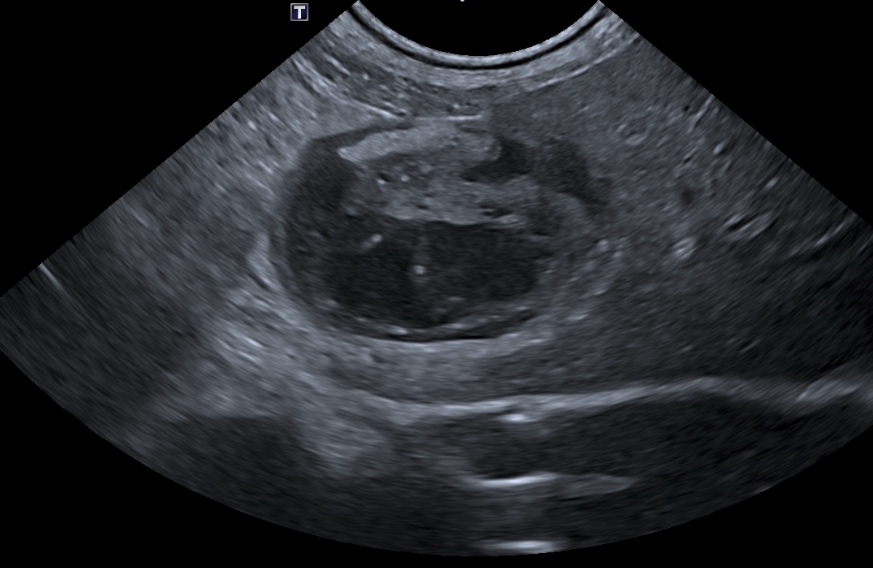

Jour 1 : Le système digestif, vaisseaux et nœuds lymphatiques tributaires.

• Rappeler l’écho anatomie du tube digestif, des vaisseaux et des nœuds lymphatiques tributaires

• Savoir décrire les images anormales du tube digestif, des vaisseaux et des nœuds lymphatiques tributaires

• TP d’échographie sur chats

• Interpréter exercices dirigés de reconnaissance et description d’images normales et anormales du tube digestif, des vaisseaux et des nœuds lymphatiques tributaires.

• TP d’échographie sur chats.